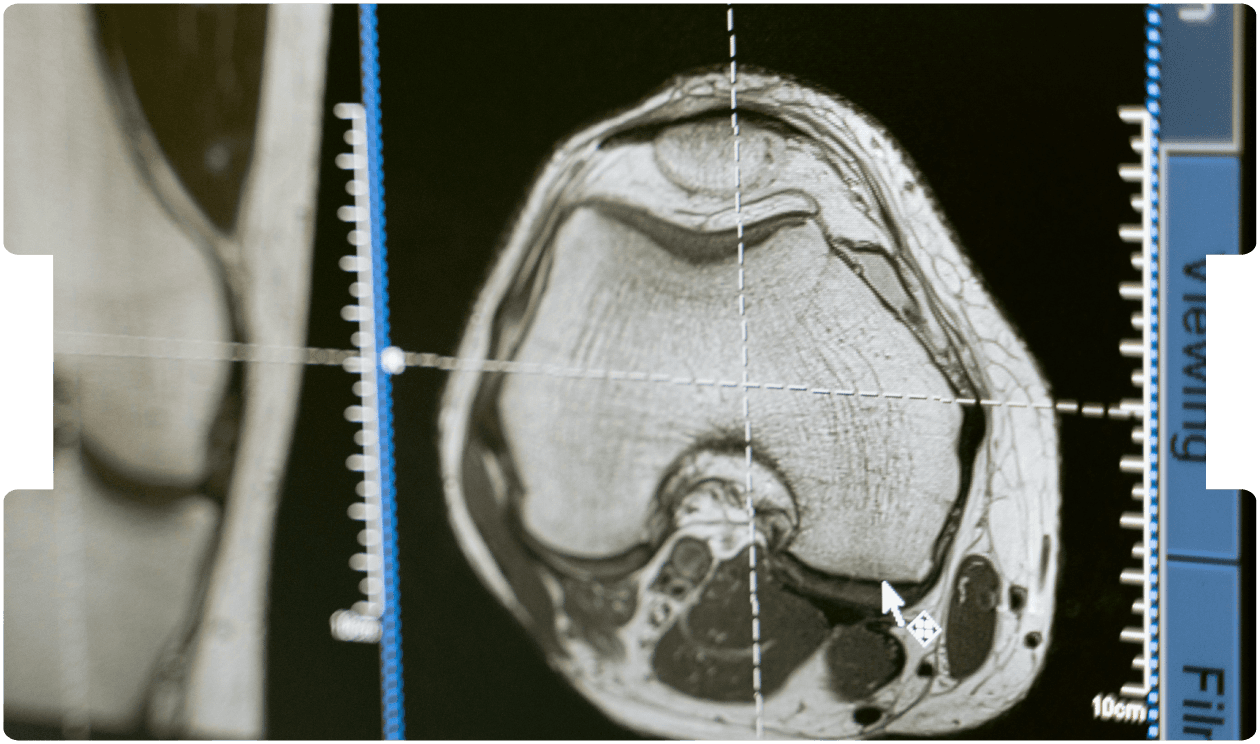

Mild Traumatic Brain Injury: When Normal Scans Hide Serious Impact

- Traumatic Brain Injury

- Brain Imaging Litigation